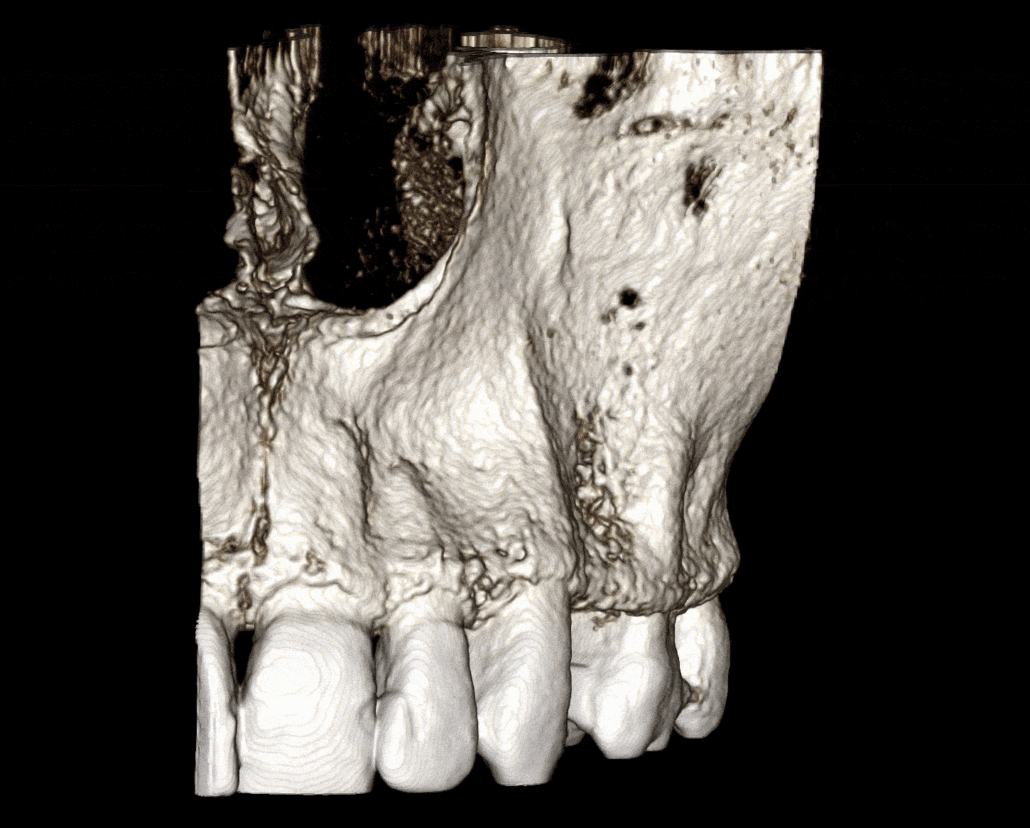

Region imaged:

UR1 – UL6

The UL4 region has mild loss in vertical ridge height. The buccal cortical plate is thin or absent. There is Misch 4 bone density (Image 2).

The remaining teeth have mild to moderate generalized alveolar bone loss due to periodontal disease.